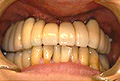

Q 実際にT-typeを臨床に用いられた症例における感想をお聞かせください。

また抜歯即時症例にも数例適応しましたが、すべて良好な経過をたどっています。 通常の症例にもT-typeは対応することが可能だと考えますが、フィクスチャー12?のものがあればさらに適応症例が広がると考えています。